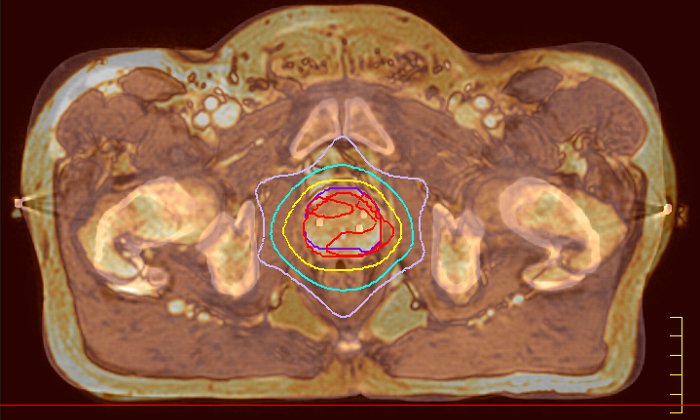

Innovative strategies in MRI-only simulation have made it possible to derive CT-like electron density information from MR imaging data. This capability enables physicians to use MRI as the radiotherapy department’s primary imaging modality for specific applications to eliminate tedious and error-prone CT-MR registration and simplify workflows.

This not only extends the benefits of MRI’s excellent soft-tissue contrast to radiotherapy planning, but it also eliminates arduous, error-prone CT-MRI registration from the process, reducing uncertainties and complexity. MR-only radiotherapy

Our innovative MRCAT (MR for Calculating ATtenuation) clinical applications lets you plan radiation therapy using MRI as primary imaging modality. Within just one, fast MR exam, MRCAT provides both excellent soft-tissue contrast for target and OAR delineation and CT-like density information for dose calculations.